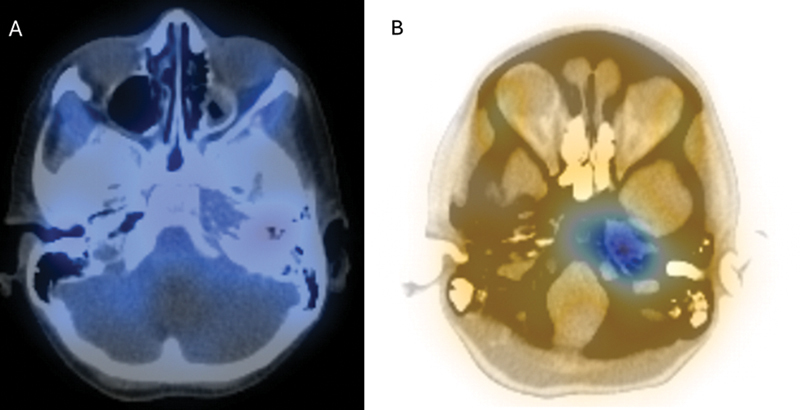

横纹肌肉瘤(Rhabdomyosarcoma, RMS)是一种罕见的恶性肿瘤,每100万儿童中有4.58例发生,约35%发生在头颈部。颅底RMS通常出现在晚期,由于其与其他颅底病理的重叠特征以及难以进入病变进行活检而延误诊断。本病例说明了这些挑战在颅底RMS模拟骨髓炎的岩尖。病例:一名6岁免疫功能正常的女性,有两次急性中耳炎病史,有3周的第6脑神经麻痹史和突然发作的完全性第7脑神经麻痹史。她没有疼痛或耳漏。计算机断层扫描(CT)和磁共振成像显示一个1.3厘米的左岩尖增强病变,延伸到乳突和斜坡,周围的骨和软组织破坏。核医学扫描(锝-99m和镓)显示左侧岩尖摄取旺盛。有效诊断为颅底骨髓炎,为此患者接受了2.5周的抗生素治疗。未能改善后,重复影像学显示疾病明显进展,并扩展到鼻咽和蝶窦。内镜下经蝶窦活检与RMS病理一致。胸部CT示肺转移。患者对用长春新碱、放线菌素- d和环磷酰胺交替使用长春新碱和伊立替康的化疗有部分反应。在化疗的第13周,她接受了总剂量5040 cGyRBE的质子治疗。确诊5个月后,她出现脑膜轻散,并进一步并发脑膜炎,最终去世。

Rhabdomyosarcoma (RMS) is a rare malignant tumor, affecting 4.58 per 1 million children, with approximately 35% occurring in the head and neck. Skull base RMS commonly presents at advanced stages and delays diagnosis due to its overlapping features with other skull base pathology, and difficulty accessing the lesion for biopsy. This case illustrates these challenges in skull base RMS mimicking osteomyelitis of the petrous apex. Case: A 6-year-old immunocompetent female, with a history of two acute otitis media episodes, presented with a 3-week history of sixth cranial nerve palsy and sudden-onset complete seventh cranial nerve palsy. She did not have pain or otorrhea. Computed tomography (CT) and magnetic resonance imaging revealed a 1.3 cm left petrous apex enhancing lesion with extension into the mastoid and clivus with surrounding bony and soft tissue destruction. A nuclear medicine scan (Technetium-99m followed by gallium) demonstrated avid uptake in the left petrous apex. The working diagnosis was skull base osteomyelitis, for which the patient received 2.5 weeks of antibiotics. After failing to improve, repeat imaging showed significant progression of the disease and extension into the nasopharynx and sphenoid sinus. An endoscopic trans-sphenoidal biopsy was performed with pathology consistent with RMS. CT chest revealed lung metastases. The patient partially responded to chemotherapy with vincristine, actinomycin-D, and cyclophosphamide alternating with vincristine and irinotecan. During week 13 of chemotherapy, she received concomitant proton therapy to a total dose of 5040 cGyRBE. Five months after diagnosis, she developed leptomeningeal spread, which was further complicated by meningitis, and passed away.